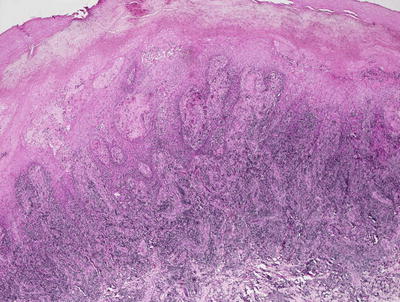

Histologic changes include a lobular proliferation of keratinocytes that contain eosinophilic cytoplasmic inclusions with a very characteristic appearance (Figs. 12.11 and 12.12). The inclusions begin in suprabasilar keratinocytes, and become progressively larger and more basophilic with upward progression in the epidermis. The epidermis is acanthotic with variable amounts of spongiosis. Transepidermal elimination is seen in many cases. An intense inflammatory response is present, and this is accentuated following rupture of the lesions. In some cases, atypical CD8+ lymphocytes and CD30+ cells are present within the infiltrate, leading to concern for lymphoma [10, 87]. Similarly, an intense inflammatory response has been identified in patients with altered immune systems [88]. Follicular involvement is commonly seen in immunosuppressed patients [4, 89].

Fig. 12.11

The epidermis is acanthotic and has a lobular appearance with abundant viral inclusions within keratinocytes in molluscum contagiosum